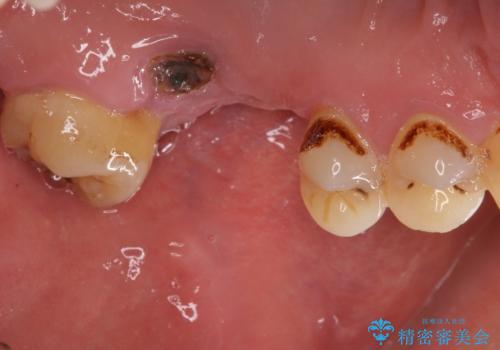

- 前歯や奥歯の虫歯を放置しており、それらの治療を契機に真っ白な歯にしたいとのことで来院された患者様です。

咬み合わせを改善するに当たって、抜歯しなければならない歯や歯列の改善が必要な箇所があったため、矯正治療やインプラント治療から始めていくこととしました。